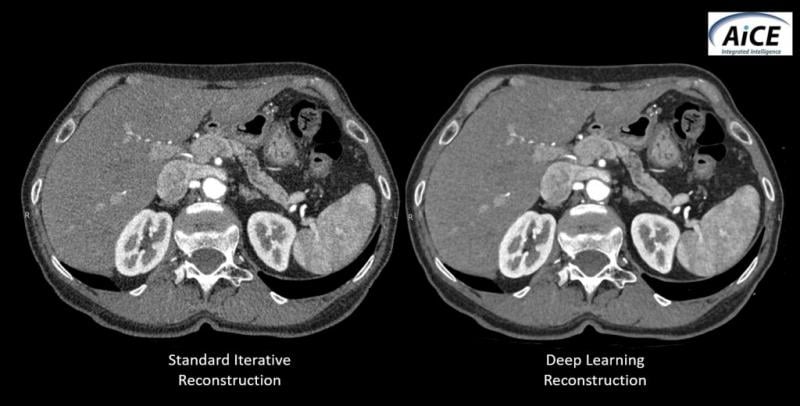

Comparison between CT images reconstructed using standard iterative reconstruction software and Canon’s new work-in-progress deep learning algorithm, called AiCE (Advanced intelligent Clear IQ Engine).

At its booth (South Hall 1938) at RSNA 2018, Canon Medical is showcasing an artificial intelligence algorithm that “learns” to improve the resolution of CT images. The algorithm, which is pending FDA clearance, uses deep learning technology to tell the difference between noise and signal. It then uses what it has learned to suppress noise and enhance signal, according to the company.

Called Advanced intelligent Clear IQ Engine or AiCE (pronounced ACE), the still experimental algorithm learns to reconstruct CT images from the high quality images produced using model-based iterative reconstruction (MBIR). Although experience with the new algorithm is limited, AiCE has the potential to set a new standard for image reconstruction in CT, according to the company.